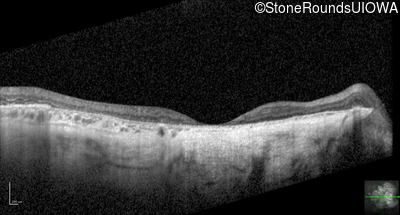

Optical Coherence Tomography - Left - 20/500

Exemplar / OCT Stack